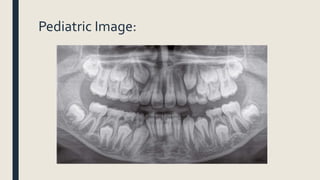

Pediatric Image:

Intraoral Imaging

OcclusalView offers a clear view of the floor of the mouth to show the bite of the upper or lower

jaw.This kind of X-ray highlights children’s tooth development to show the primary (baby) and

permanent (adult) teeth